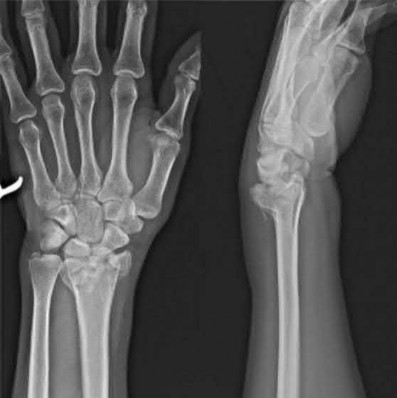

Question 6:

A 22-year-old male falls onto an outstretched hand and sustains a displaced fracture through the proximal pole of the scaphoid. Avascular necrosis of the proximal pole is highly likely due to the disruption of its primary vascular supply. Which vessel provides this critical retrograde perfusion?

Correct Answer: Dorsal carpal branch of the radial artery

Explanation:

The primary blood supply to the scaphoid is from the dorsal carpal branch of the radial artery, which enters the dorsal ridge of the scaphoid at the waist and courses proximally. This retrograde blood flow makes proximal pole fractures highly susceptible to avascular necrosis and nonunion. The superficial palmar branch provides a minor supply (about 20%) to the distal pole.